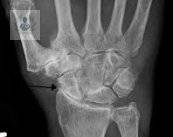

Osteoporosis: Una enfermedad silenciosa que debilita los huesos

La Osteoporosis es una condición que afecta la salud ósea y puede pasar desapercibida durante años. Su importancia radica en que aumenta de forma significativa el riesgo de Fracturas, lo que puede modificar de manera importante la calidad de vida.